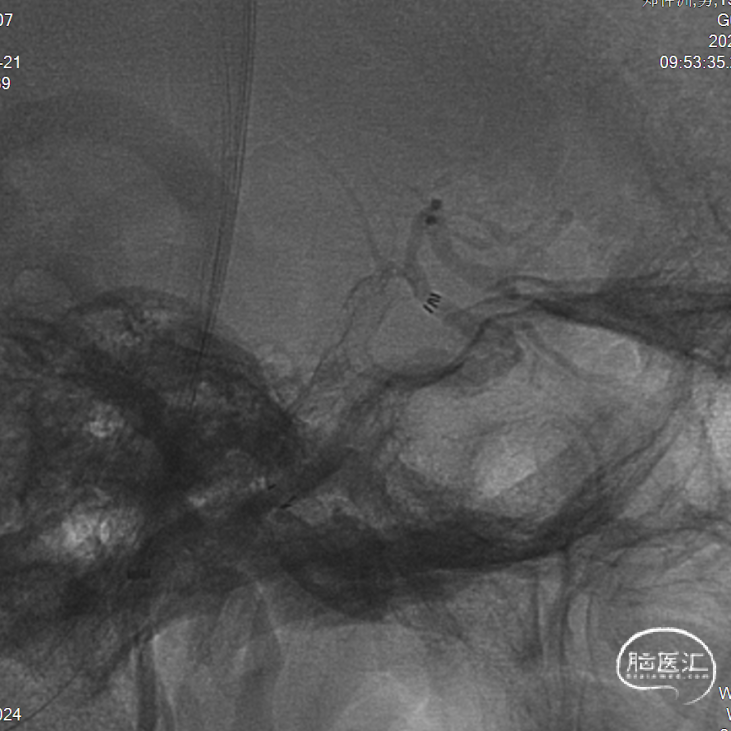

微导丝+SL-10微导管超选至大脑中动脉,行导丝交换技术置Rebar微导管,沿微导管送入加奇4*30mm Syphonet®取栓支架,在颈内动脉终末段释放行远端保护。抽吸导管回抽可见回血,轻推造影示颈内动脉多发重度狭窄。

沿Syphonet®取栓支架输送导丝送入3*15mm Maverick球囊,分段扩张。

造影示颈内动脉狭窄改善,后撤指引行造影证实颈开口无明显狭窄。

使用6F抽吸导管回收加奇Syphonet®取栓支架,使用SWIM技术将支架及导管撤出,可见支架附着大块暗红色血栓。

造影见颈内动脉海绵窦段一血栓影,mTICI分级2B级。将6F Sofia导管送至海绵窦段行负压抽吸,未见回血及血块。